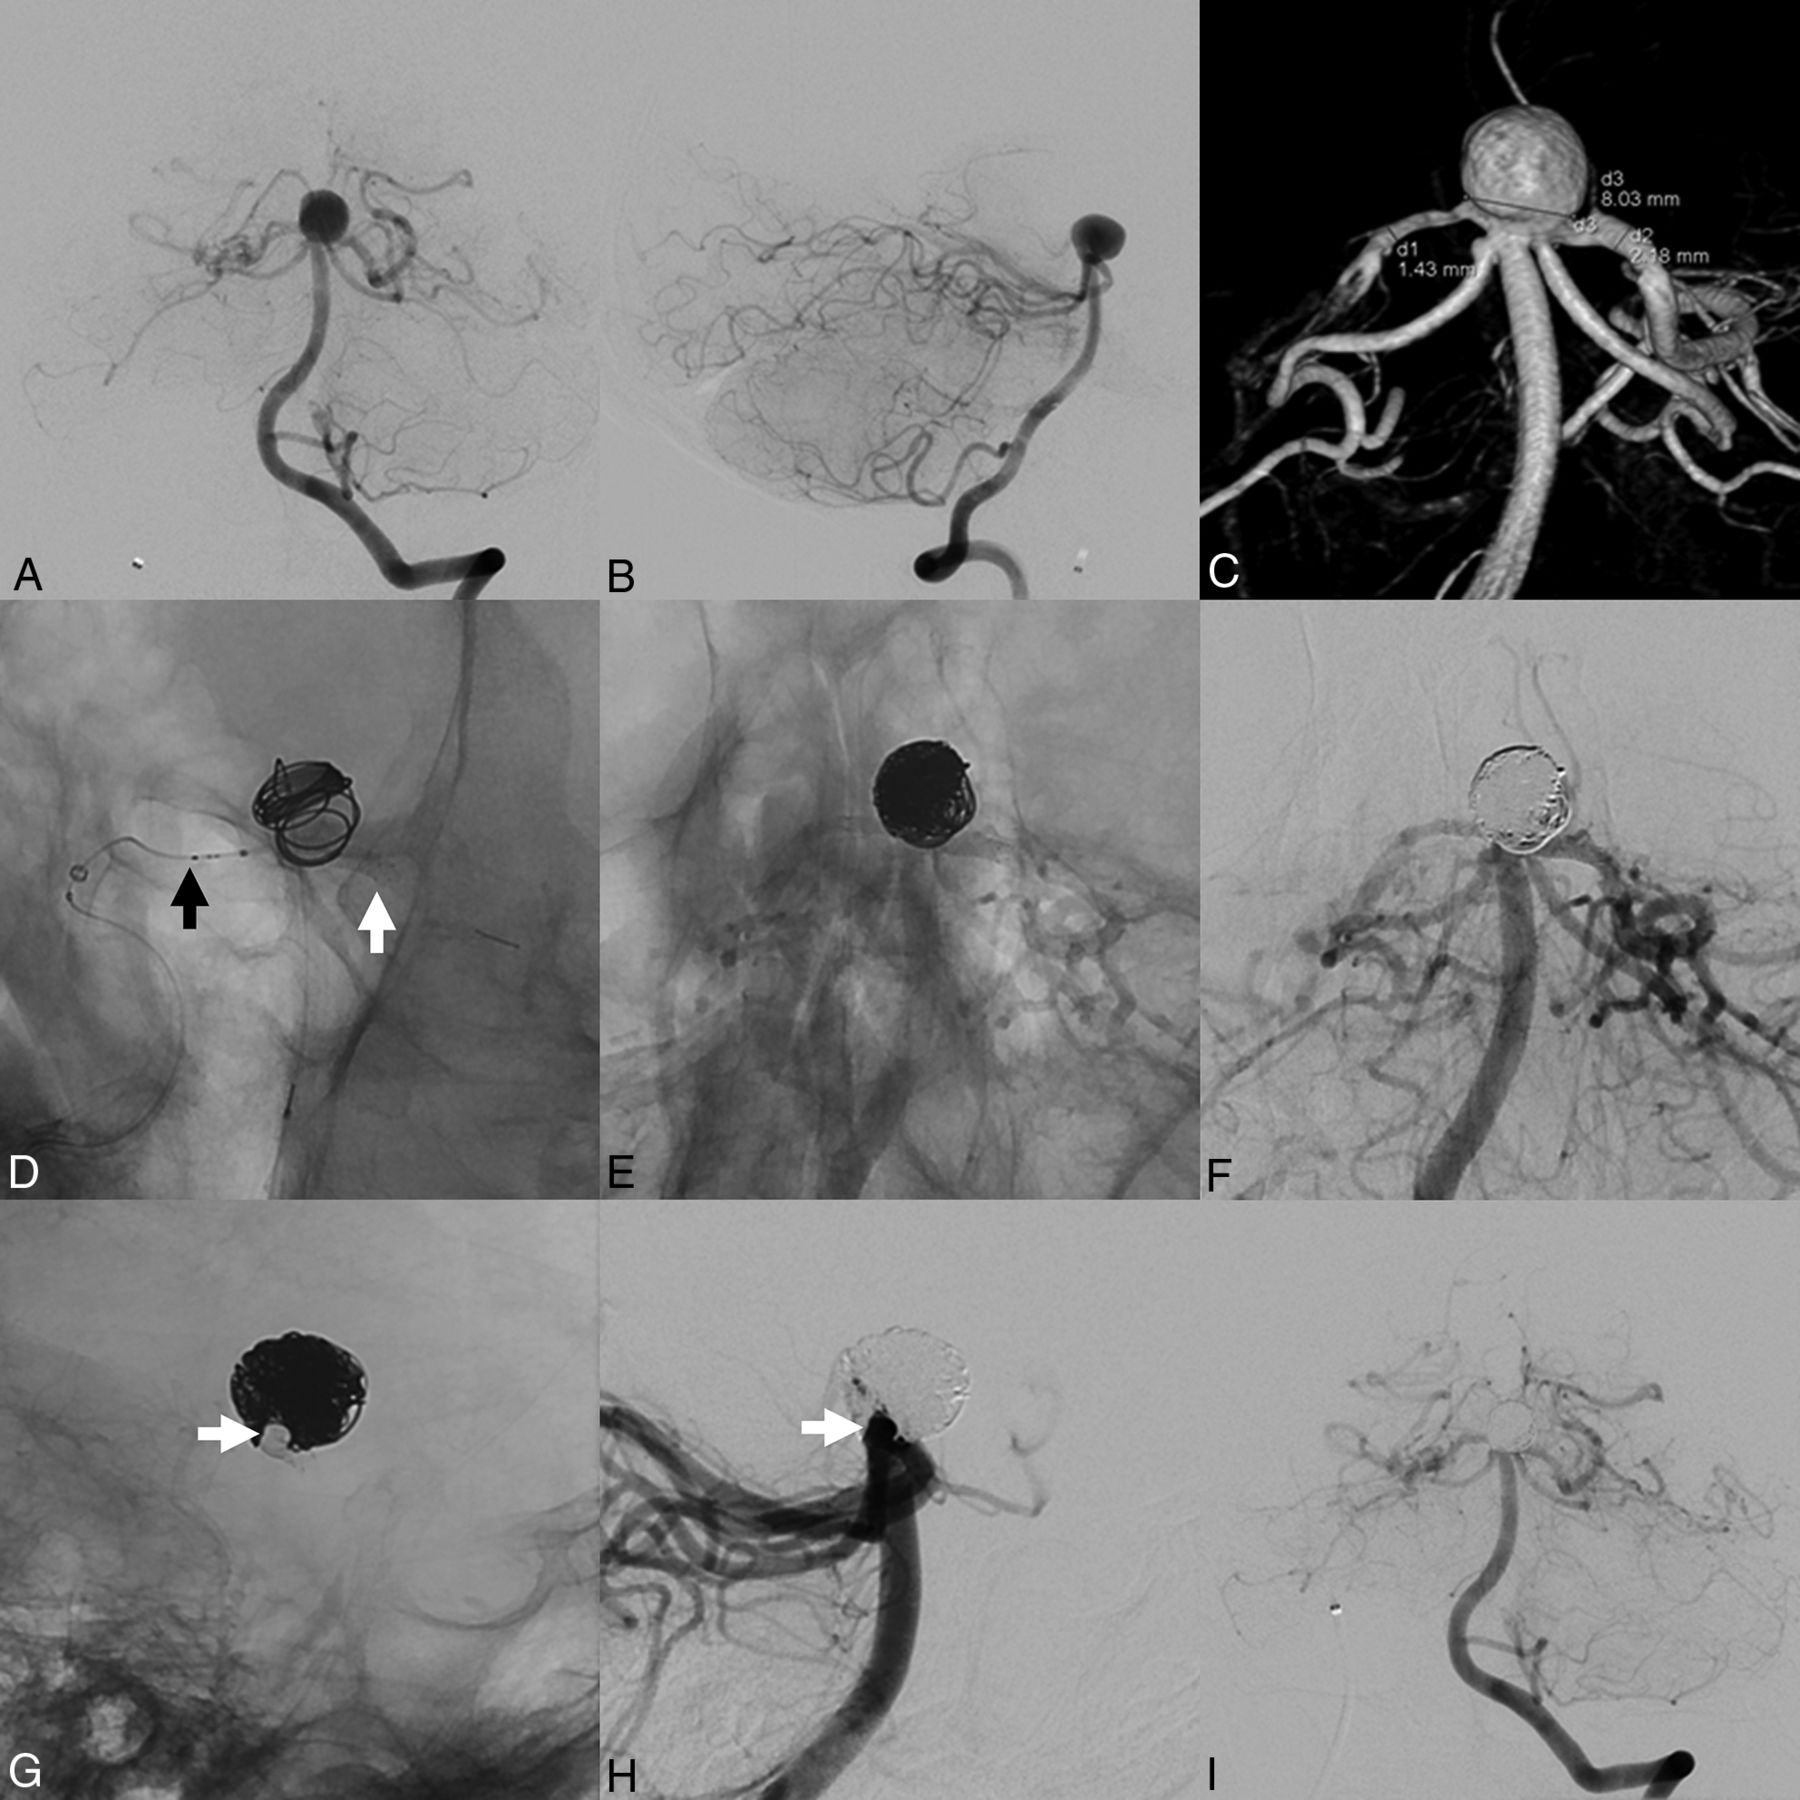

Stent-assisted coiling of an incidental aneurysm of the AcomA. DSA (A) and 3D reconstructions of rotational angiography (B and C) show a wide-neck aneurysm of the AcomA. After positioning of a microcatheter within the aneurysm (black arrow in D), a 3 × 18 mm LVIS EVO stent was deployed in the A1 and A2 segments of the left ACA (stent ends marked with white arrows). Shouldering of the stent at the base of the aneurysm (black arrowheads) enabled protection of the aneurysmal neck. Subsequently, the aneurysm was coiled (E and F). The shouldered stent enabled complete protection of the parent artery at the aneurysmal neck (black arrows in E) and remodeling of the parent artery. DSAs after treatment (G–I) show complete occlusion of the aneurysm.